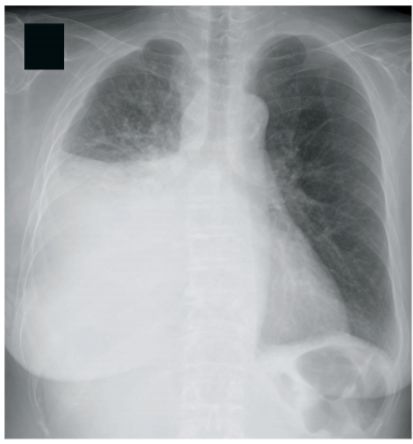

29 61 歳の女性。息苦しさを主訴に来院した。年前に乳癌に対し右乳房温存乳腺 部分切除術を受けて以来、抗癌化学療法とホルモン療法とを続けている。週前か ら息苦しさを自覚し、徐々に増悪してきたため受診した。体温 36.8 ℃。脈拍 108/分、整。血圧 120/80 mmHg。呼吸数 24/分。SpO2 90 %(room air)。右胸部で 呼吸音が減弱している。下腿に浮腫を認めない。血液所見:赤血球 410 万、Hb 11.8 g/dl、Ht 38 %、白血球 7,200、血小板 21 万。免疫学所見:CRP 0.3 mg/dl。 CEA 9.2 ng/ml(基準以下)。マスクで酸素投与を開始したところ、SpO2は 95 % になった。胸部エックス線写真(別冊No. 3)を別に示す。 現時点の対応として適切なのはどれか。 (A)気管挿管 (B) 胸腔刺 (C)強心薬の投与 (D)抗菌薬の投与 (E) 心囊刺